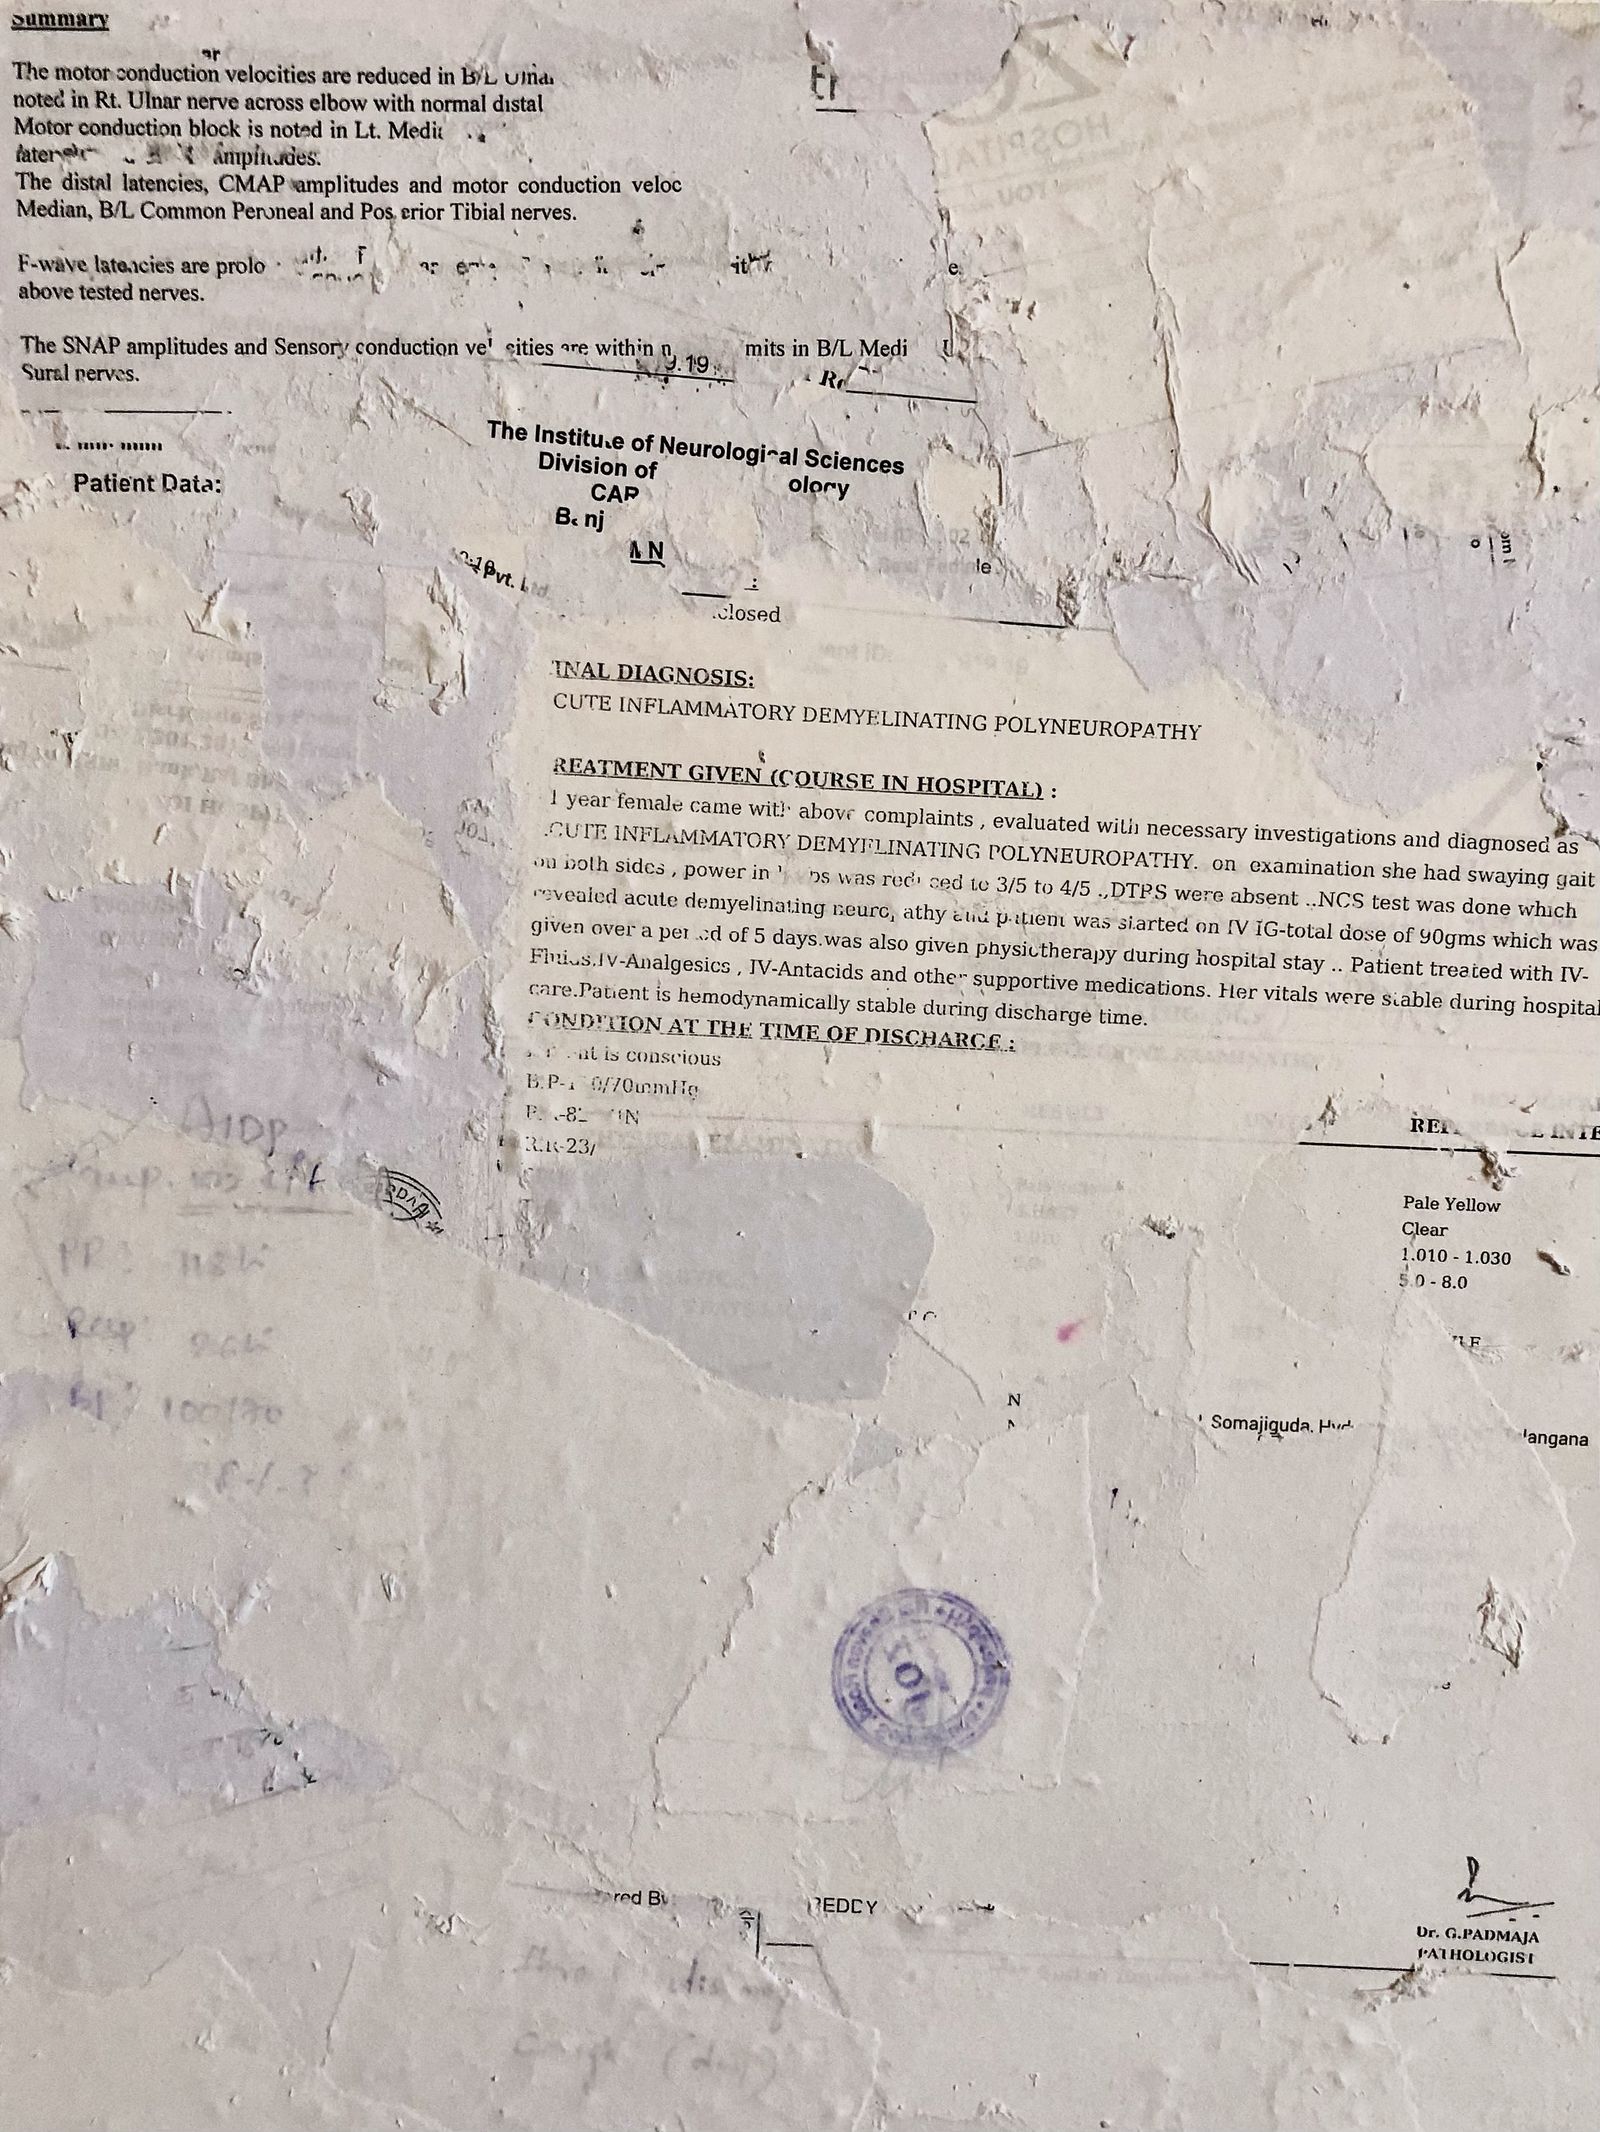

In July 2019, I was diagnosed with Guillain-Barré Syndrome, a rare neurological condition that quickly brings you to complete paralysis. Eventually, I regained movement, but I did not recover the same way inside. My body healed, yet I remained estranged from it. This disconnection between my body and soul continues to shape how I live.

There Is No Other Home emerges from the space between chaos and understanding. My body often feels like it carries its own memory. My hands loose grip, I stumble more often, and I freeze at things others take for granted, like driving. I return to fragments of memory, my mother’s CT scan when she was carrying me and my twin sister, a childhood photograph, not as evidence of illness but as traces of fragility, endurance, and survival.

There Is No Other Home is an ongoing project that continues to evolve, exploring the dialogue between conscious memory and embodied memory through experimentation with photography, sculpture, text, and scanning. My practice remains open to new forms and materials as I deepen my inquiry into trauma, body, and healing, while questioning the boundaries of visual and tactile storytelling.